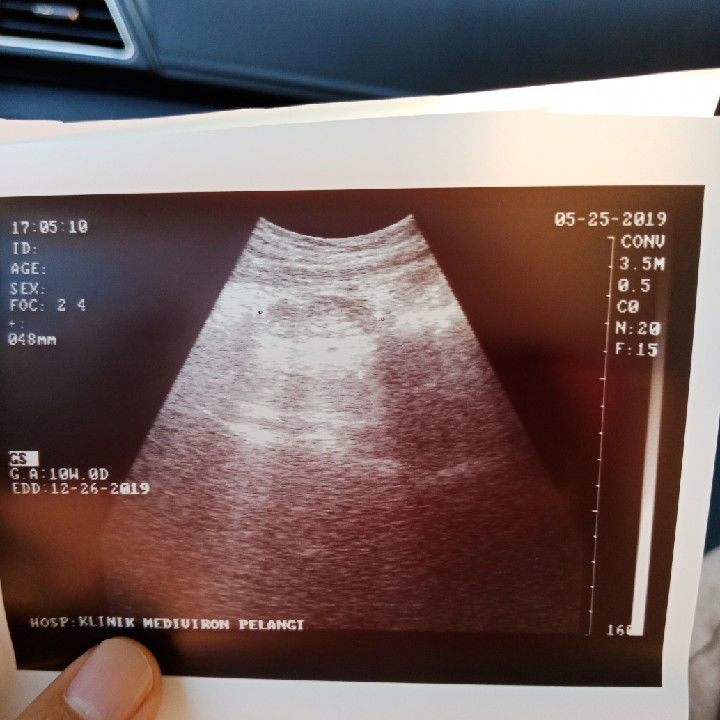

1st Baby Scan

Hi, look at my 10 weeks baby. It was difficult for the doctor to locate my lil diva sebab dia menyorok dekat belah kiri. Alhamdulillah doktor kata heartbeat dia very active. Tapi lil diva saya macam terapung. Normal je kan kedudukan dia macam ni? So excited and curious!